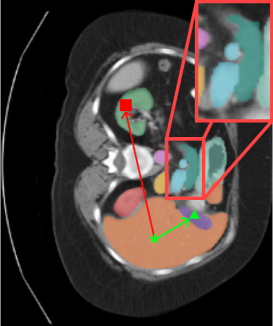

Refer to caption

Figure 5: Qualitative results of the proposed model. The region of interest was highlighted with arrows. (From left: GroundTruth, DTS(our), UNet, SwinUNETR, Diff-UNet)

6 Comparative Results

As shown in Table.6, we compare our model with the BTCV benchmark dataset. Compared with other models, the proposed DTS achieves the best performance and presents a higher dice result of 0.906. It can be seen that previous diffusion segmentation models show comparable performance to conventional segmentation models in relatively large organs(e.g. liver, stomach), but poor performance in small organs(e.g. esophagus, aorta). DTS surpasses the closest competing methods by an average of 2% across all classes, with an even more significant improvement of 7% specifically for gall bladder. We believe that our approach and the application of the high performance transformer architecture will lead to improved accuracy. Comprehensive qualitative results of our model, which demonstrate good segmentation performance for small organs, can be found in Fig.5, highlighting our model’s ability to capture details and achieve accurate boundary representations.